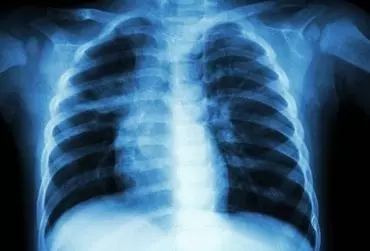

Rola wyciągu z bluszczu w infekcjach dróg oddechowych u dzieci

Bluszcz jest rośliną stosowaną od wieków w terapii infekcji, ale stosunkowo niedawno odkryto, iż liście bluszczu Hedera hedelix zawierają hederakozyd C i jego pochodne saponiny – alfa-hederynę, czyli substancję, która jest odpowiedzialna za jego farmakologiczne działanie: wykrztuśne, rozkurczające oraz sekretolityczne. Dzięki tym właściwościom wyciągi bluszczu stosowane są w leczeniu infekcji układu oddechowego.